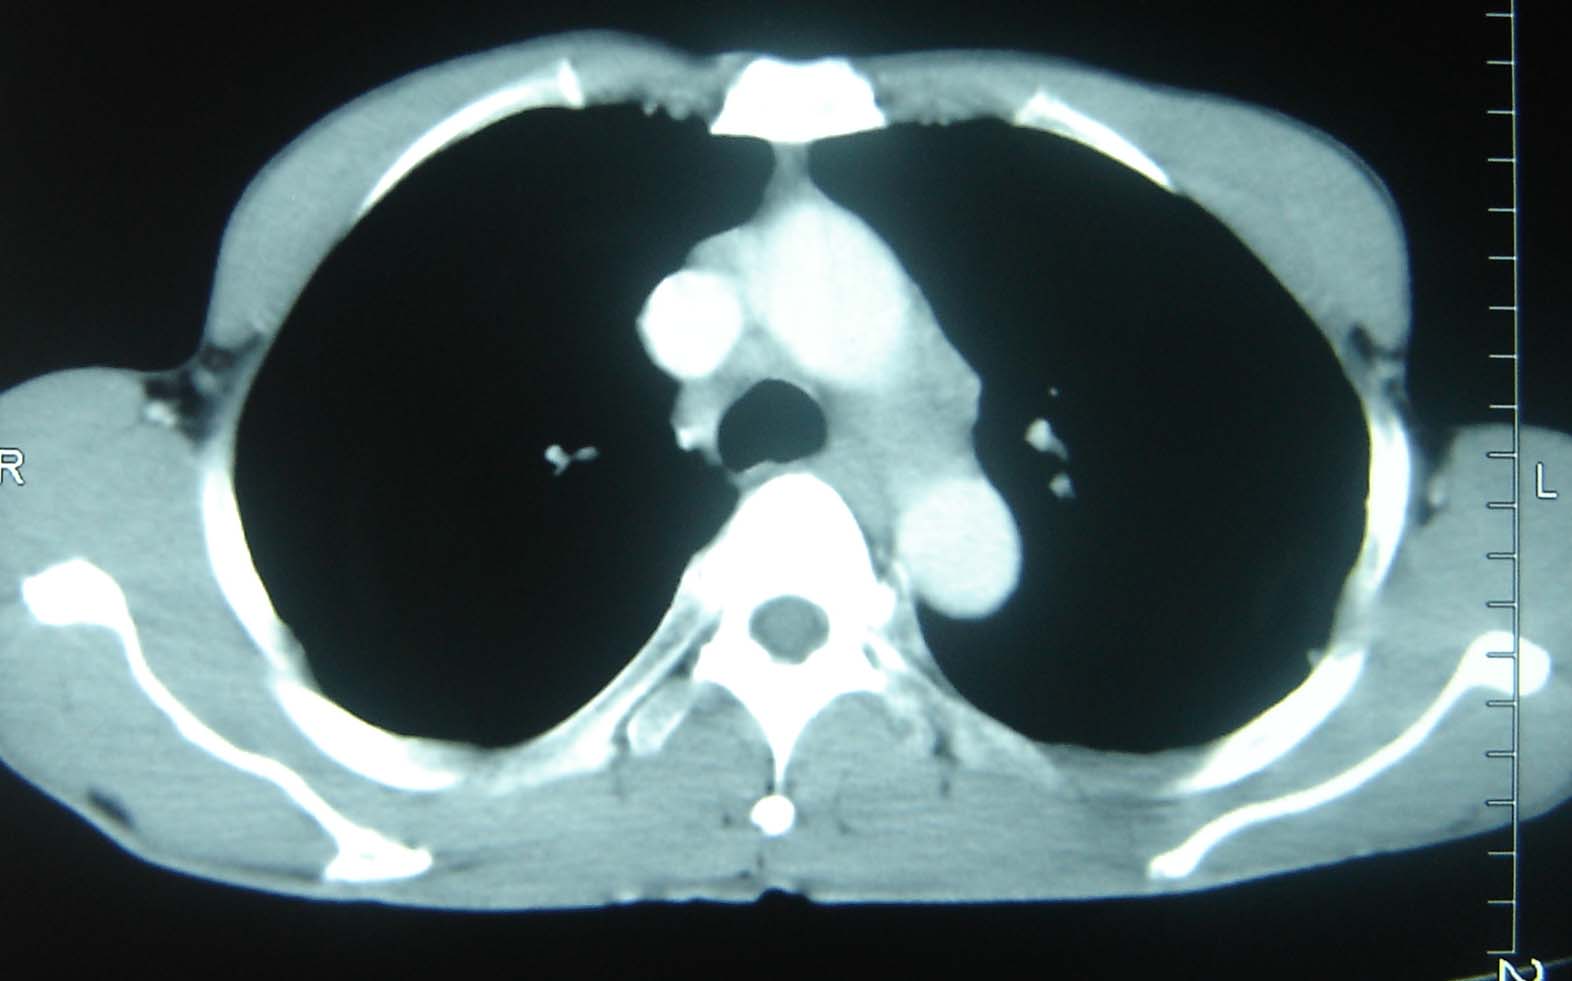

男 、43岁,咳嗽胸痛,装修工,平时接触粉尘较多,有吸烟史10多年,纤维支气管镜检查未发现异常,胃镜、腹部b超检查亦未发现异常,颈部淋巴结活检未发现肿瘤细胞。

不能排除转移,如果不能找到原发灶,只有短期随访。

结节病?转移瘤?

结节病。

转移瘤?

转移

1)考虑双肺及胸膜多发性转移瘤。2)肺气肿。

双肺结节病。